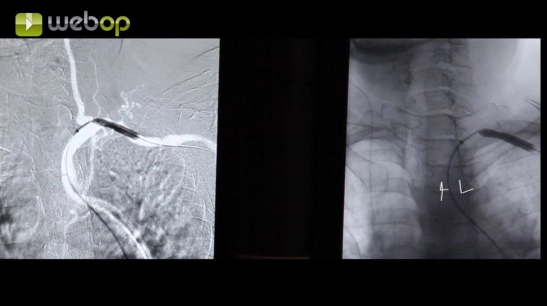

Aorta und Beckenstrombahn

Perkutane transluminale Angioplastie mit Stentimplantation bei Nierenarterienstenose bds.